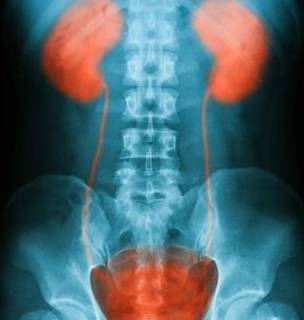

说到肾积水 , 可能有很多人不知道 , 那么今天就来带领大家一起认识 。 首先要说的就是肾积水是关于肾脏器官的疾病之一 , 这种疾病出现之后若不及时治疗 , 就会对人体造成一定的危害 。

所以大家患了肾积水的这种疾病之后就要积极的进行治疗 , 那么该如何治疗呢 , 下面就来一起看看吧 。 肾积水有两类治疗方法 , 这两类方法都是目前为止最为有效健康的 , 接下来就为大家详细的介绍:

这种手术的治疗方式是在疾病已经无法用保守治疗的方法缓解的时候 , 不得已而实施的一种手术 , 这种手术的实施是为了清除肾脏中无法排出的尿液 , 在手术过程中医生会在身体上打开一个小口 , 让肾脏里面的尿液不通过输尿管而是直接从这个小口里面拍出来 。 不过这个手术有个缺点就是做了之后病人需要是终身悬挂一个集尿袋 , 这对于很多病人来说都是非常痛苦并且难以接受的一件事 。

肾积水治疗的目的就是要把肾脏中无法排泄出的尿液排出体外 , 通过以上的手术方式治疗之后可以最大程度的保存人体的肾脏 。 如果病人身体的肾积水病情轻微 , 没有引起身体其他部位严重的副作用 , 那么在肾脏功能逐渐恢复之后 , 就可以直接移除掉这种悬挂的装置 , 从而让人体恢复肾功能正常的排泄功能 。

肾积水是因为人体内的结石所引起的 , 那么就可以先进行碎石或取石手术之后 , 让输尿管恢复通畅 , 这样人体内的肾积水病情就可以得到治疗 。 有些人可能是肾管和肾盂的位置先天性的就很狭窄 , 这个时候就需要去做相关的手术治疗 , 修复好之后病情也能够得到治疗 。